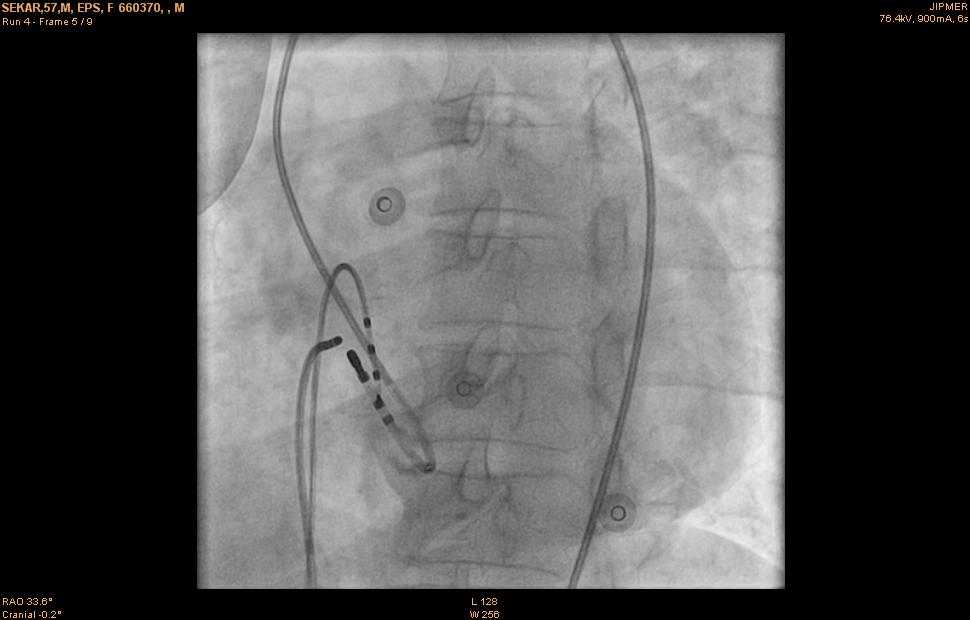

Ablation

09_ablation.jpg